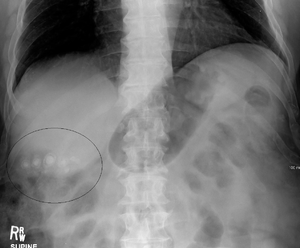

Gallstones found incidentally on KUB (xrays are not sensitive).